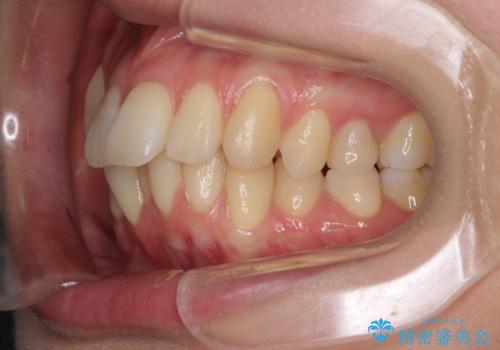

- 上の前歯、および下の歯列全体のでこぼこを気にして来院された患者様です。

インビザラインを用い、IPR(歯と歯の間を削る)と歯列全体を後方に移動させることで、歯並びを整えていくこととしました。

歯列全体を後方に移動させるため、下顎の親知らず2本を抜歯することとしました。